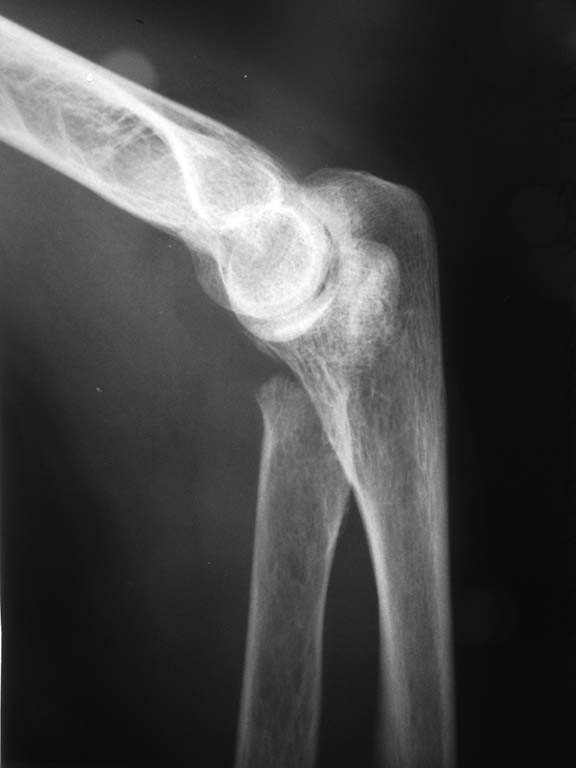

Здравствуйте, всем доброй ночи. Поступила женщина 50 лет. Перелом шейки лучевой кости слева. Чрезмыщелковый перелом плеча слева. Перелом лучевой кости слева со смещением+ шиловидный отросток локтевой кости.

Перелом мыщелков установлен автором сообщения, по снимкам во вложении его также можно предположить

Перелом головки луча с полным ее смещением и разворотом ее под углом 90 градусов

Протезирование головки возможно более перспективно в плане функции, хотя будет интересно услышать мнение коллег

Чрезмыщелкового перелома плеча не видно.. Головку лучевой вернуть на место и синтезировать (если есть чем). Дистальный луч то же синтезировать.

Много смотрел - множественных переломов локтя не обнаружил. Боюсь показаться глупым, но на мой взгляд головку луча можно вернуть на место путём открытой репозиции без обширных диссекций. Вариант фиксации, по-моему мнению - ретроградный ИМО. Я бы выбрал два TEN 2,5-3 мм. Остеопороза не видно. Женщина не старая. Эндопротезирование никуда не денется. Дистальный луч можно по-всякому стабилизировать. С уважением!

Совершенно верно, уважаемый Сергей Юрьевич. Ретроградно, можно и через дистальный отломок луча с предварительной его репозицией. У детей с подобными переломами такое получается. Головка по предъявленным снимкам сломана субкамитально, отломок - вся головка + развёрнута на 90 градусов. Можно, конечно, репонировать закрыто с джойстиком или леватором. Нейлинг, на мой взгляд, совсем не ухудшит судьбу головки и позволит как можно раньше начать движения в суставах предплечья.